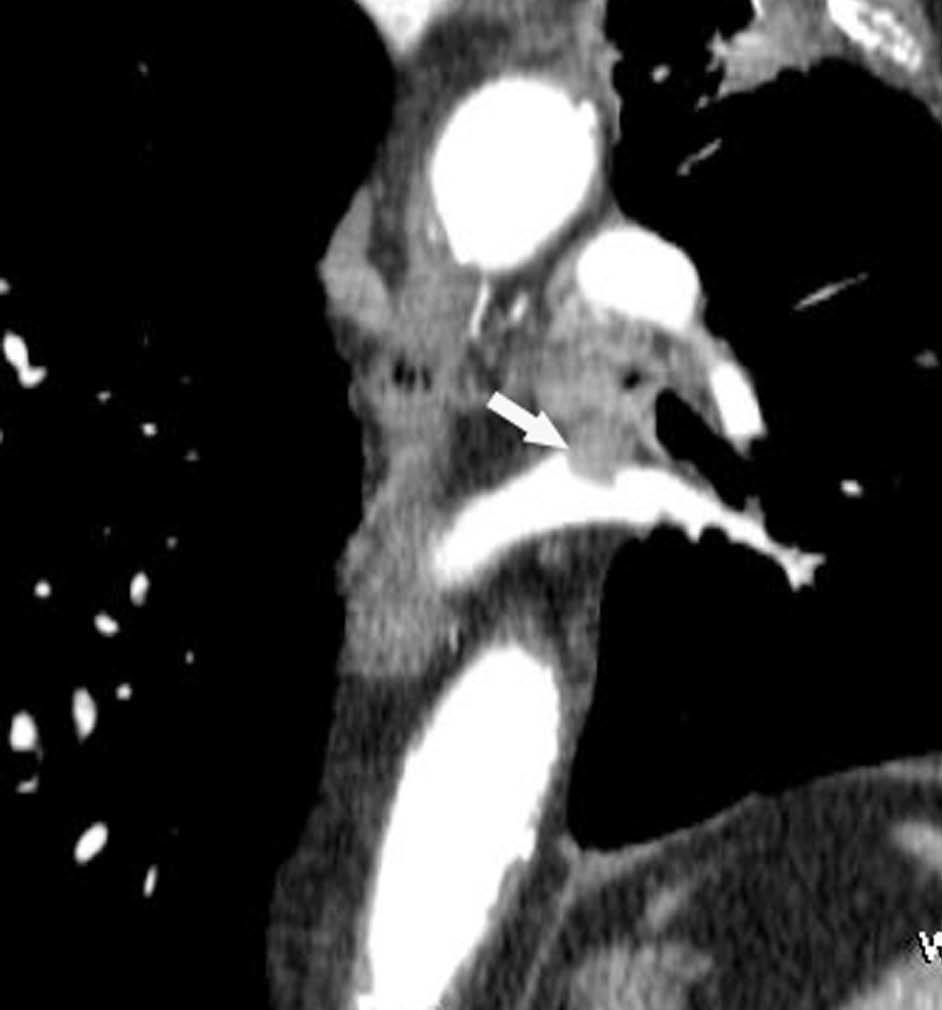

Valoración del tumor

El estadio tumoral (T) se basa en el tamaño, localización y relación con las estructuras adyacentes valorado mediante TC. Los tumores T1 son aquellos de 3 cm o menores en su diámetro mayor, rodeados de pulmón y que no invaden la pleura visceral ni los bronquios principales, mientras que los T2 son lesiones mayores de 3 cm, o aquellas que invaden la pleura visceral o al bronquio principal a más de 2 cm de la carina o que condicionan atelectasia o neumonitis obstructiva que no afecte a todo el pulmón. La diferenciación entre ambos estadios tumorales suele ser sencilla mediante TC, salvo la afectación de la pleura visceral, aunque esta no tiene un impacto importante en el manejo clínico. El tumor T3 viene determinado por la infiltración de estructuras vecinas potencialmente resecables, como la pared torácica, diafragma, pleura mediastínica, pericardio parietal o si el tumor está situado a menos de 2 cm de la carina (fig. 1). Los tumores T4 son aquellos que no pueden ser resecados porque engloban a estructuras vitales, invaden el corazón, grandes vasos, esófago o cuerpos vertebrales (fig. 2) o en los que existe un nódulo o nódulos en el mismo lóbulo del tumor. Además de definir la T, es importante reflejar las particularidades de la infiltración de estructuras en vecindad que puedan modificar la actitud terapéutica. Por ejemplo, cambiará la estrategia quirúrgica según el tipo de bronquio afecto o la estructura mediastínica infiltrada, si es sólo la grasa, o un vaso; cuando existe neumonitis o atelectasia secundaria a un tumor central, la planificación del campo de radioterapia dependerá del límite entre la masa y la repercusión pulmonar.

Fig. 1.--T3. (A) Reconstrucción multiplanar (MPR) de tomografía computarizada (TC) torácica con contraste con ventana de pulmón. Atelectasia completa del lóbulo inferior derecho secundario a tumor endobronquial situado a menos de 2 cm de la carina (flecha hueca). (B) La misma reconstrucción con ventana de mediastino muestra el tumor (flechas) diferenciado de la atelectasia (asterisco). Derrame pleural (DP).

La diferenciación entre tumores T3 y T4 puede ser difícil empleando sólo técnicas de imagen. Cuando se evidencia destrucción ósea (costal o vertebral), existe masa en el espacio intercostal (fig. 3), o las estructuras mediastínicas están claramente englobadas por el tumor, el diagnóstico es obvio (fig. 2). Sin embargo, sin estos hallazgos, la predicción de invasión es mucho menos fiable. Se han descrito diferentes signos que pueden ayudar a determinar la invasión de pared torácica. Éstos incluyen el contacto con la superficie pleural mayor de 3 cm, el engrosamiento pleural, la ausencia de plano graso y la presencia de un ángulo obtuso entre el tumor y la pared torácica. Aplicando al menos dos de estos criterios la sensibilidad es de un 87%, sin embargo la especificidad es baja (59%)4. El dolor torácico localizado es un síntoma importante que a menudo está asociado a invasión de pared.